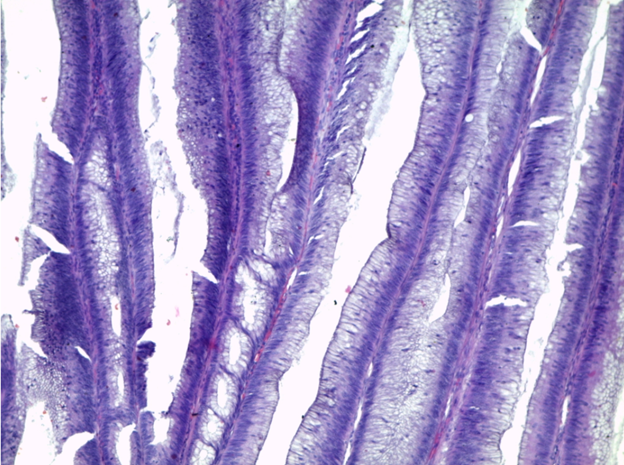

Препарат № 381

АДЕНОКАРЦИНОМА В ВОРСИНЧАТОЙ АДЕНОМЕ ТОЛСТОЙ КИШКИ

Окраска: гематоксилин-эозин

Полиповидное опухолевое образование толстого кишечника из пролиферирующего железистого эпителия с признаками дисплазии, покрывающего ворсинчатые выросты – аденома. В опухоли определяются очаги инвазивной внутрислизистой аденокарциномы в виде плохо сформированных сливающихся железистых комплексов из атипичного эпителия. В крае препарата сохранена нормальная слизистая толстой кишки.

Отметить:

1. Ворсинчатая аденома

2. Аденокарцинома

3. Нормальная слизистая.